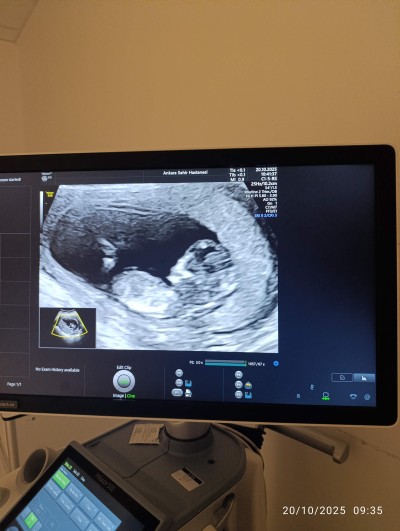

13 haftalık hamileyim 26 aylık bir oğlum var bunu çok merak ediyorum tahminleribekliyorum☺️

Bence senin êrkêk canım öylê hissettim

Bence de erkek çıkıntı görünüyor ama hayirlisi